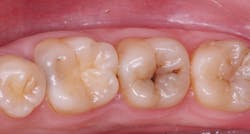

This is a well-known procedure, but it’s often confused with liners or bases. I have observed that almost all restorative dentists provide indirect pulp capping for their patients. The size and location of the dental pulp varies significantly depending on patient age and the extent of previous restorative treatment causing pulp response and reduction in pulp size (figure 1). When excavating caries, the ideal goal is to remove all observable caries without exposing the pulp. Often, the following situations occur in a typical day of practice: removal of the soft caries, dentin is hard to remove with an excavator, stained tooth structure remains, and the operator’s knowledge of dental anatomy and a radiograph indicate that a pulp exposure will occur if excavation is continued. An indirect pulp cap is placed on the deepest portions of the tooth preparation (figure 2).